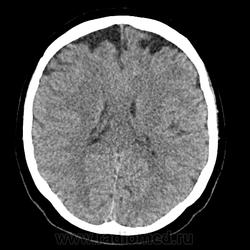

расширение субарахноидального пространства лобные области

подскажите пожалуйства как расценивать такие изменения.(девушка 1992 года)  что то ничего конкретного не нашел. Ткните если не там ищу. И если не там тему создал ((

Как вариант, конвекситальные арахноидальные кисты.

Скорее всего кисты.

в заключении писать "подозрение на кисты(жидкостные образования)" и мрт рекомендовать?